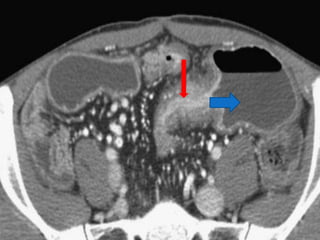

CT Enterography

The sensitivity - 82%

specificity - 89%

accuracy - 85%.

 Mural enhancement

 Mesenteric fat stranding

 The comb sign

 Pseudosacculations